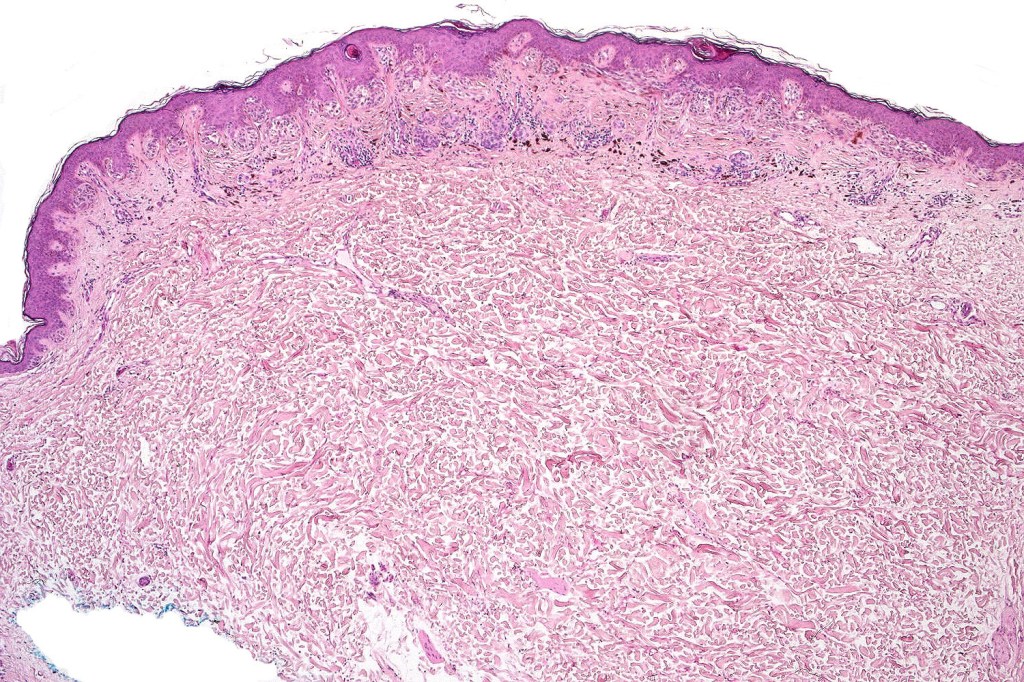

Dysplastic nevus with early melanoma

Dysplastic nevus in the majority of cases is instantly recognizable, often at low power. The most important differential diagnosis is obviously melanoma. In junctional lesions, widespread/uniform high grade atypia, frequent mitoses and Pagetoid spread are indicative of in situ melanoma. In compound lesions, dermal nests larger than junctional ones, expansile dermal nests, severe atypia and mitotic activity indicate the presence of melanoma